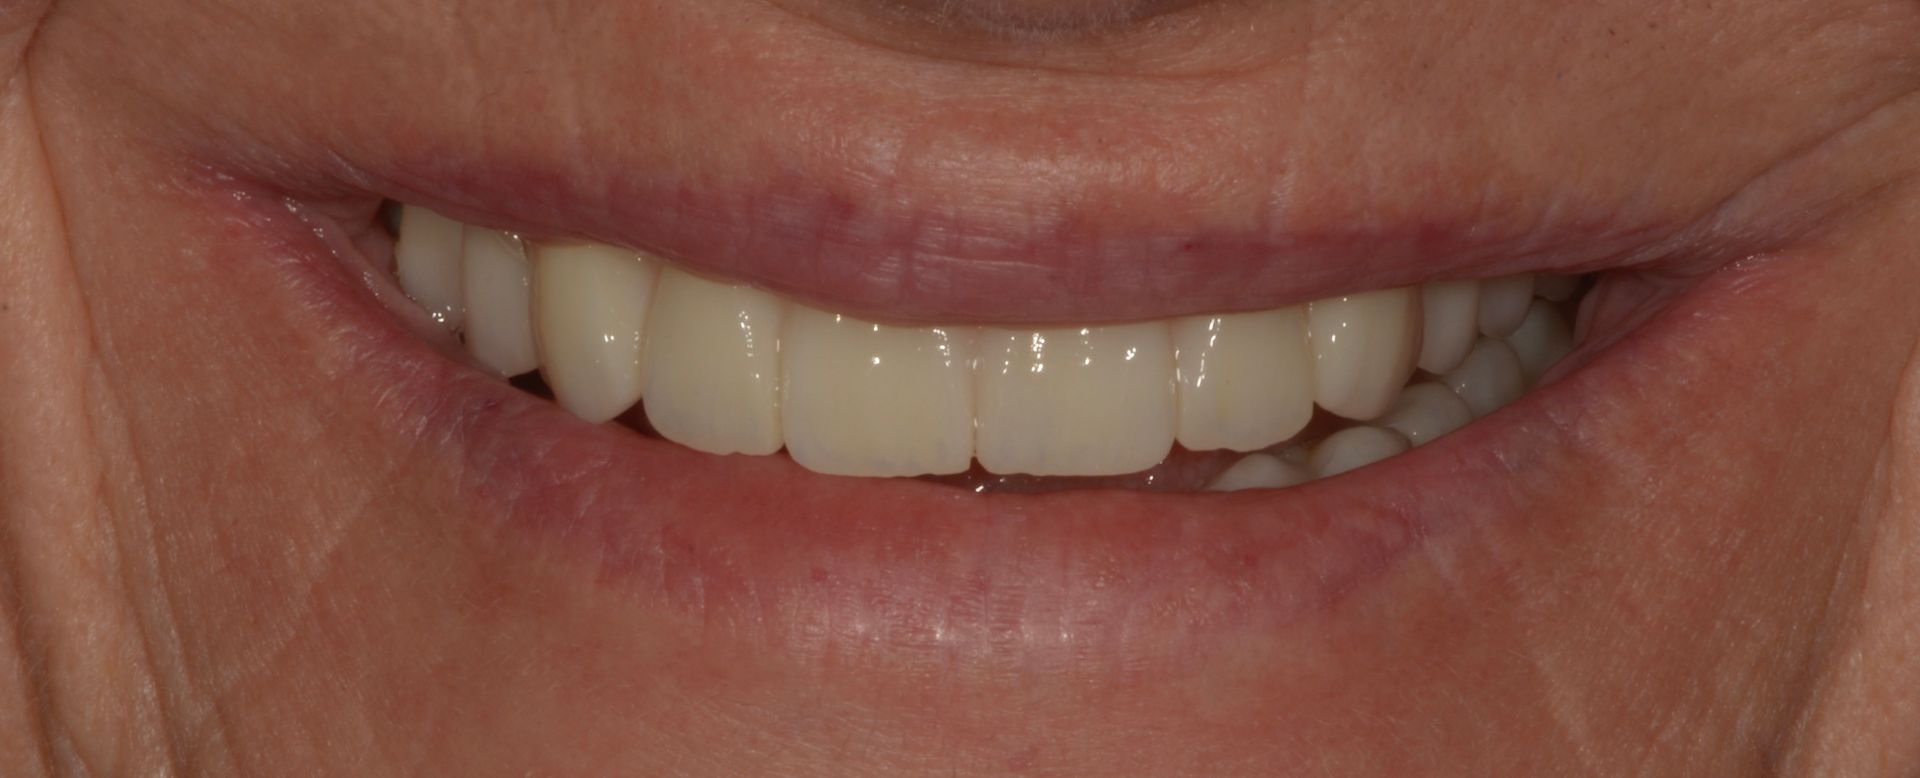

Vedi il caso qui accanto il paziente aveva vecchi impianti falliti e una protesi totale superiore e gli avevano detto che non aveva possibilità di mettere denti fissi...

Il paziente era molto amareggiato perché non tollerava la protesi totale e aveva dolori dovuti agli impianti infetti dell'arcata inferiore. Dopo un attento studio del caso, in cui sono state studiate le forme e le altezze delle nuove protesi e abbiamo eseguito una pianificazione digitale dell'intervento chirurgico impiantare abbiamo inserito 5 impianti nel superiore con una rigenerativa orizzontale e 4 impianti nell'inferiore. a distanza di 4 ore dall'intervento abbiamo caricato gli impianti con le protesi provvisorie a carico immediato fatte con resina e una struttura in titanio, a distanza di 6 mesi sono state sostituite con 2 arcate titanio zirconio.